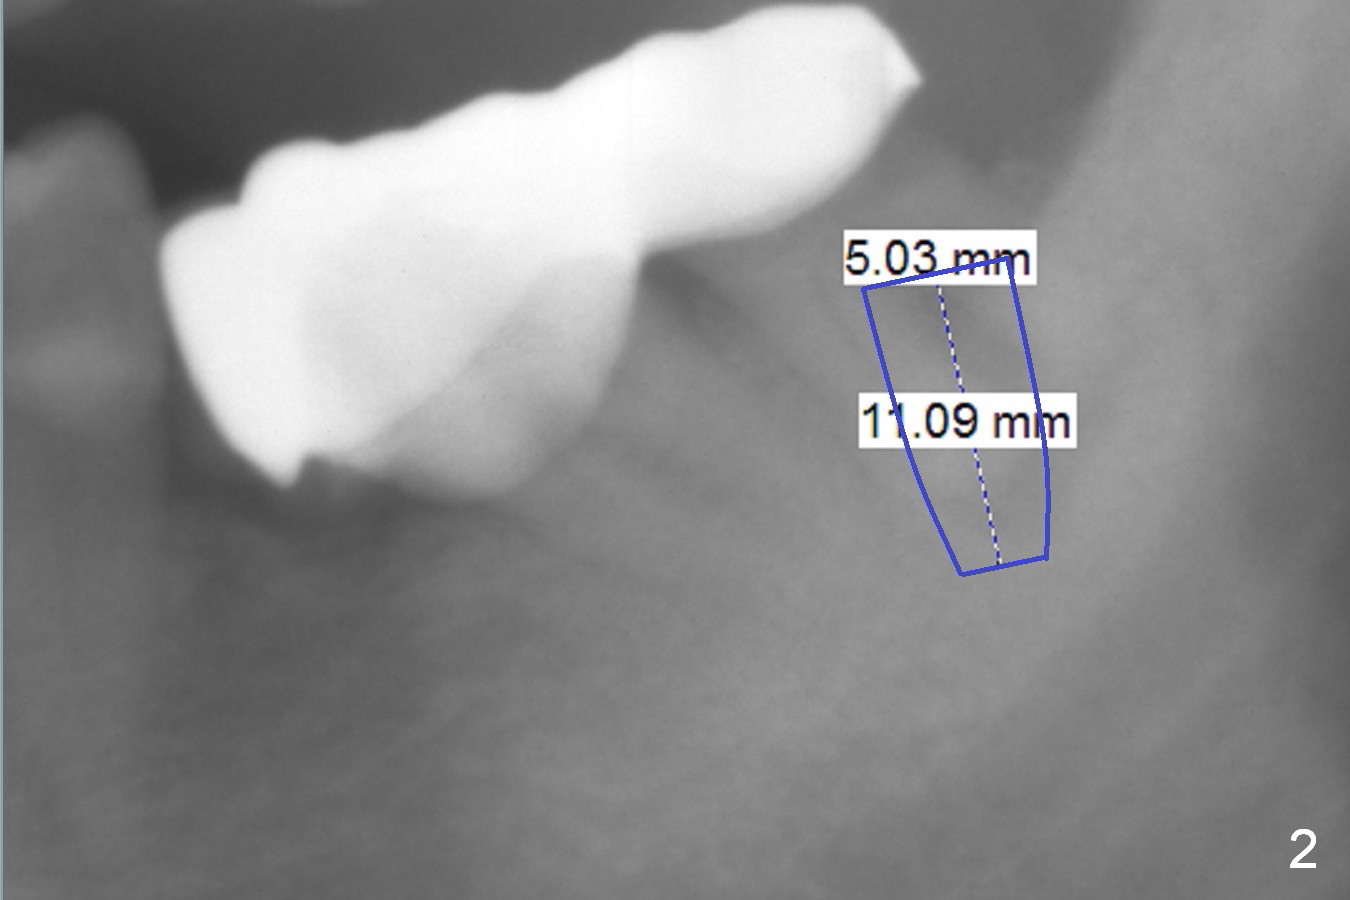

A 82-year-old man has pain in the lower left bridge. There is a buccal apical fistula associated with the tooth #17 (Fig.1). An immediate implant will be placed at #17 after bridge removal (Fig.2,3 blue). Once it osteointegrates, it will be used an anchorage (direct (instead of indirect), most efficient) to upright the tooth #18 (change the longitudinal axis from red line to purple one (Fig.4); white circle: center of resistance (rotation)). Then an implant will be placed at #19 (white rectangle).

Take Alginate impression and keep it moist. It will be used as a stent for temporization later on. After the tooth #17 is extracted with Clindamycin treatment, a FC dummy implant (5x9 mm) will be placed, followed by 6x4(2) mm abutment (Fig.3,4 pink). If there is severe vertical height issue, change to Magicore. Due to schedule conflict, prepare UF for this case instead.